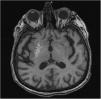

Hemiballism/hemichorea (HH) is a hyperkinetic movement disorder observed mostly in older adults with cerebrovascular diseases. Although the symptoms improve without any treatment, lesioning or DBS (deep brain stimulation) may be rarely required to provide symptomatic relief for patients with severe involuntary movements. HH is a rare complication of uncontrolled diabetes. There are only a few reported cases of diabetic HH that have been surgically treated. Thus, herein, we have reported the case of a 75-year-old female with type-II diabetes mellitus that presented with disabling involuntary limb movements of the left side, despite being treated conservatively for six months. DBS targeting the globus pallidus internus (GPi) and ventral intermediate (Vim) thalamic nucleus was performed. Complete resolution of symptoms was achieved with a combined stimulation of the thalamic Vim nucleus (at 1.7 mA) and GPi (at 2.4 mA). The combined stimulation of the Vim nucleus and GPi effectively resolved the diabetes-induced HH symptoms in our patient. Thus, although certain conclusions cannot be drawn due to the rarity of the surgically treated patients with HH, the combined stimulation is a novel treatment option for resistant HH.